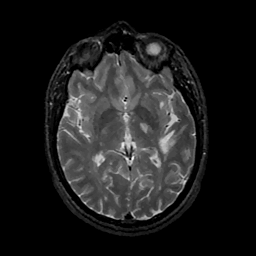

MR Study #11, May 5, 1991 -- Slice #25